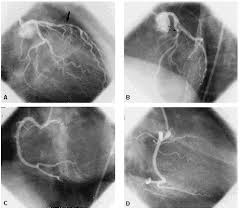

Exames: Coronariografia (código da AMB 3.09.11.07-9)

O que é o exame: consiste no cateterismo seletivo das artérias coronárias (artérias que irrigam o coração), com injeção direta de meios de contraste e realização de radiografias para visualização do fluxo de sangue através do coração.

Para que serve: investigação de doenças arteriais coronarianas, como aterosclerose, que podem causar um ataque cardíaco. O exame está indicado em pacientes com angina instável, dor torácica atípica, estenose aórtica ou insuficiência cardíaca inexplicada.

Instruções para a realização do exame: antes da coronariografia é feito o cateterismo cardíaco e o paciente recebe um sedativo leve para relaxar. Uma área corporal, geralmente o braço ou a virilha, recebe anestesia local e é feita a inserção de um cateter venoso, que é cuidadosamente conduzido até as artérias do coração.

- O paciente não pode comer ou ingerir líqüido 8 horas antes do exame.

- Deve ser assinado um termo de consentimento para a realização do exame e informar ao médico episódios prévios de alergia a frutos do mar, reações a materiais contrastados, uso de Viagra e desejo de engravidar.

Riscos do exame: a coronariografia carrega riscos levemente maiores que outros exames cardíacos, contudo é um teste bastante seguro se realizado por uma equipe experiente. Os riscos do procedimento incluem: arritmias cardíacas, tamponamento cardíaco, trauma arterial causado por hematoma, hipotensão arterial, reação ao meio de contraste, hemorragia, acidente vascular cerebral e ataque cardíaco. O material de contraste pode afetar os rins particularmente em pacientes diabéticos.

Considerações: nos casos em que se encontra um bloqueio nas coronárias, o médico pode realizar uma intervenção coronariana percutânea para a desobstrução.